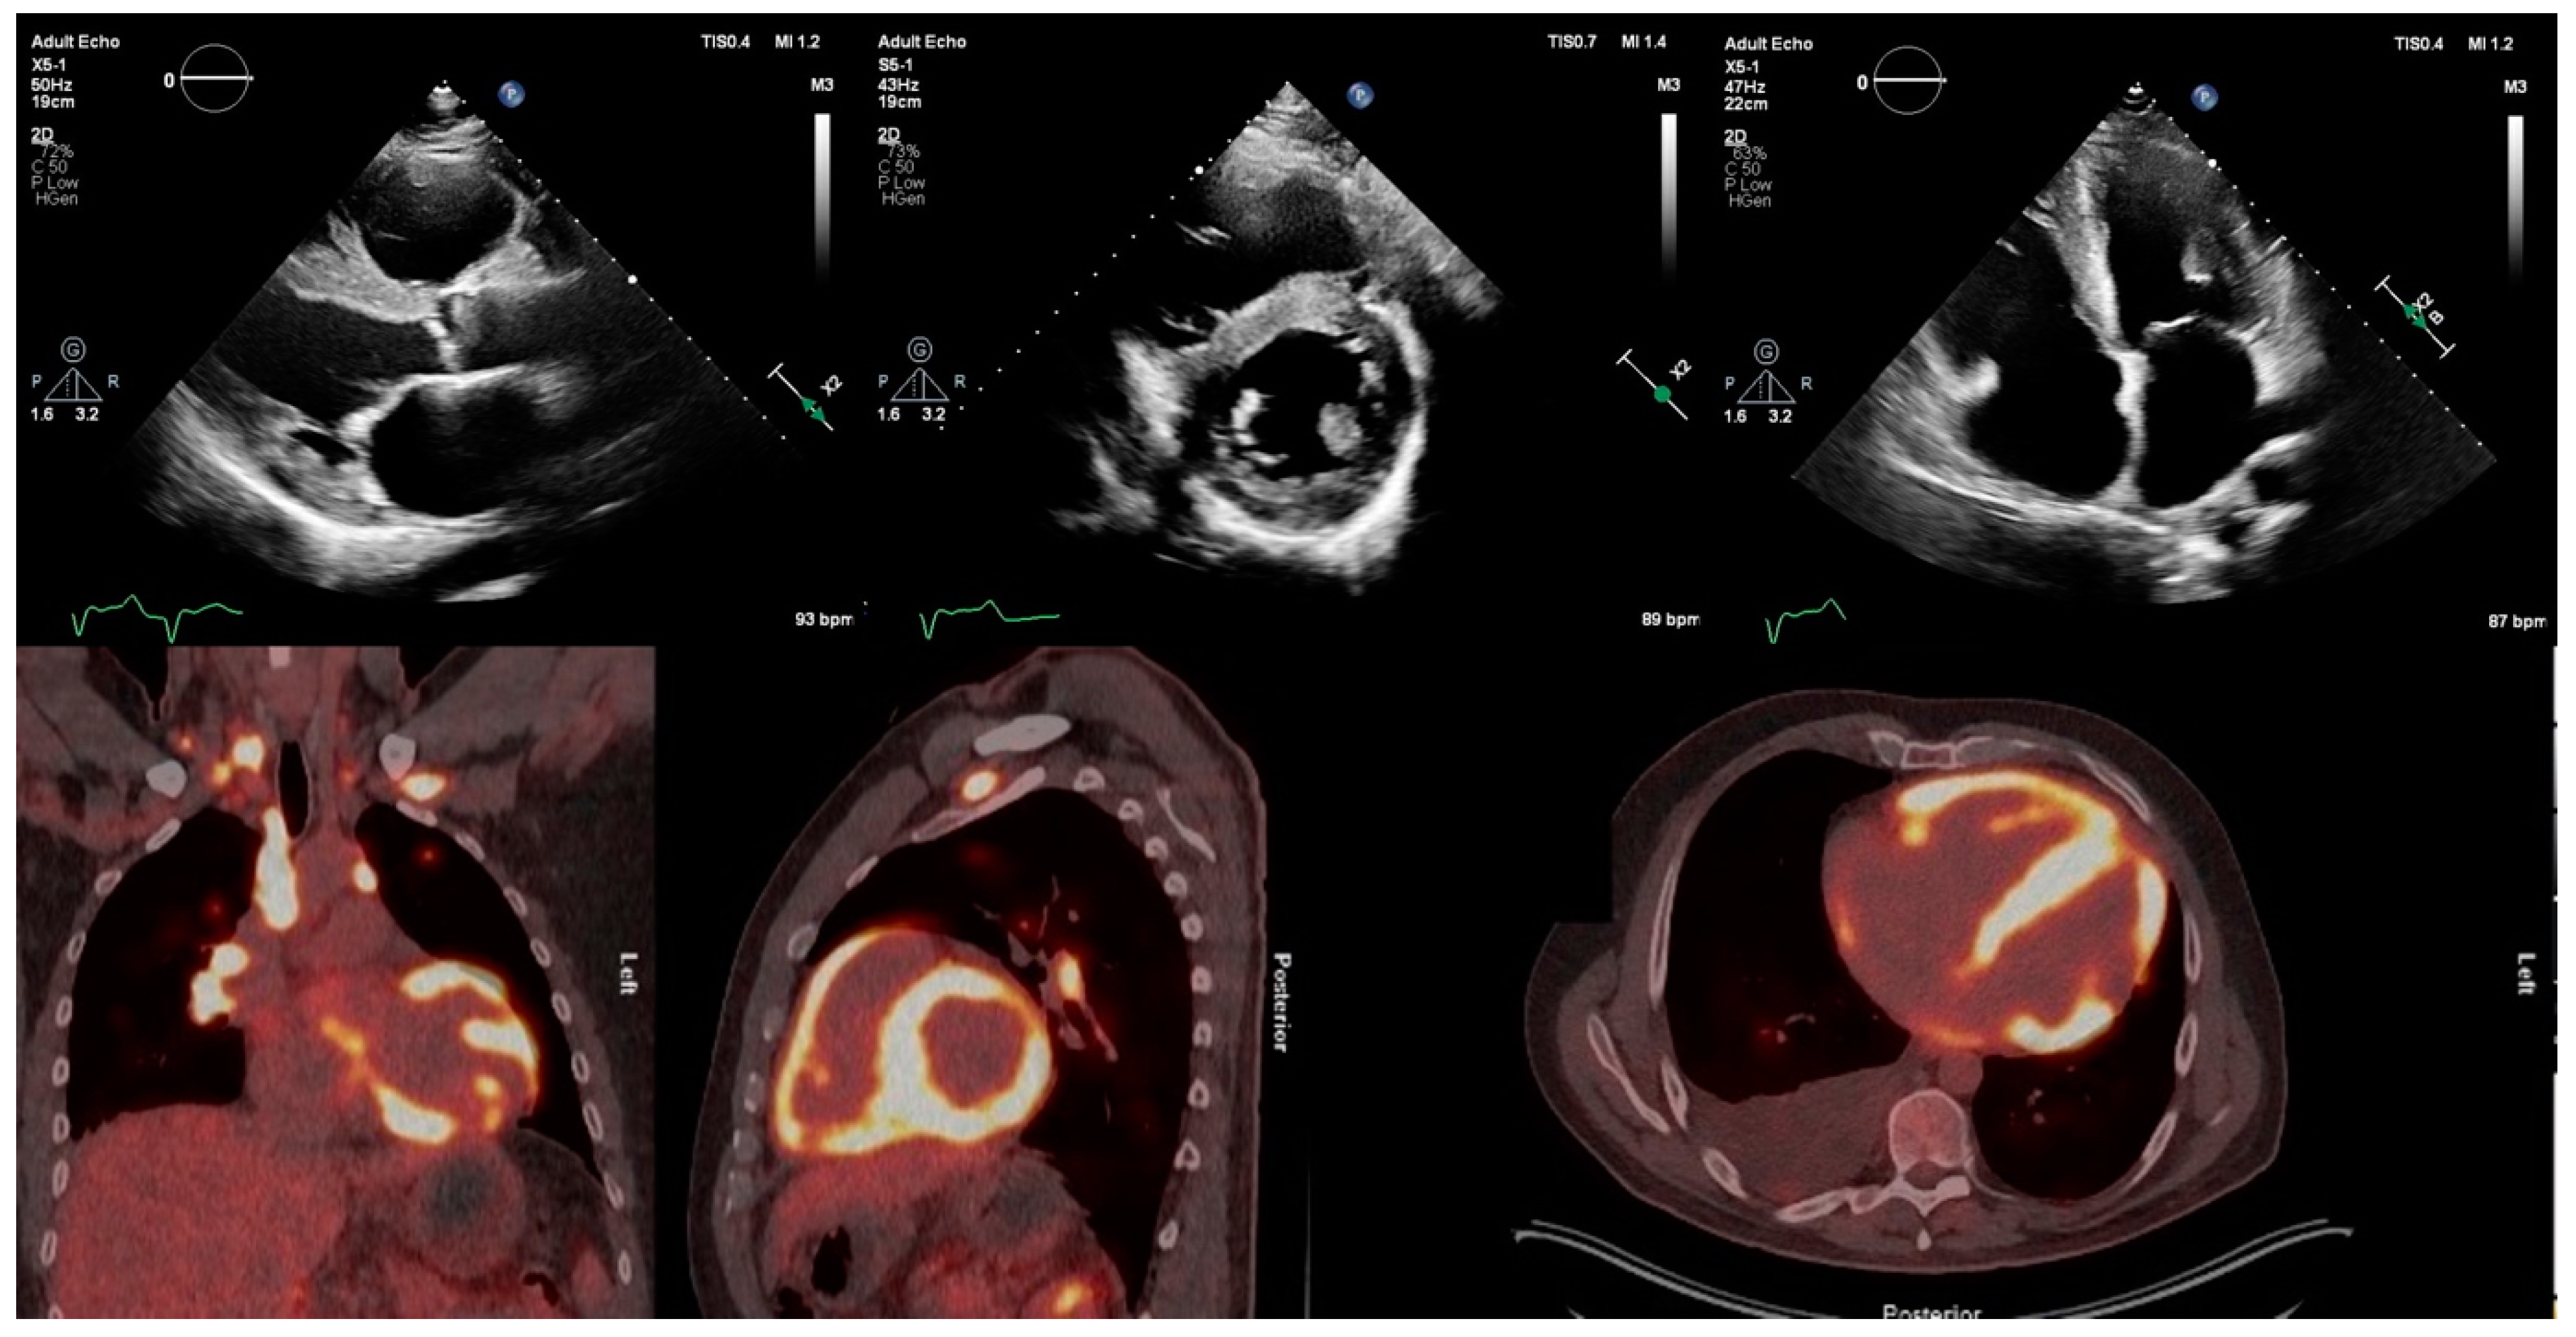

Figure 2.

Transthoracic echocardiogram of patient with active cardiac sarcoidosis demonstrating hypertrophied, echogenic speckled left-ventricular myocardium in regions with high 18F-FDG uptake on PET, particularly the interventricular septum. 18F-FDG = 18F-fluorodeoxyglucose; PET = positron emission tomography.